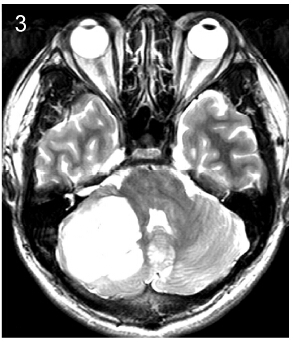

2 Patients and methods This study was approved by Ethics Committee of Tiantan Hospital, Capital Medical University. We retrospectively reviewed the medical records of all patients operated at our hospital between January 2004 and January 2007 who were diagnosed with medulloblastoma and were aged 16 years or older at diagnosis. Follow-up data were collected by telephone or follow-up visits at the clinic.Tumor location was defined as central or lateral on the basis of preoperative computed tomography and magnetic resonance neuroimaging findings and surgical reports (Figures 1-3). Because infiltration of the floor of the fourth ventricle was only observed in cases of centrally located tumors, we classified the tumors into three subtypes: those located at the midline without infiltration of the fourth ventricle floor, those located at the midline with infiltration of the fourth ventricle floor, and those located laterally.

| Figure 2 Subtype 2, midline-located tumor with fourth ventricle floor infiltration. |